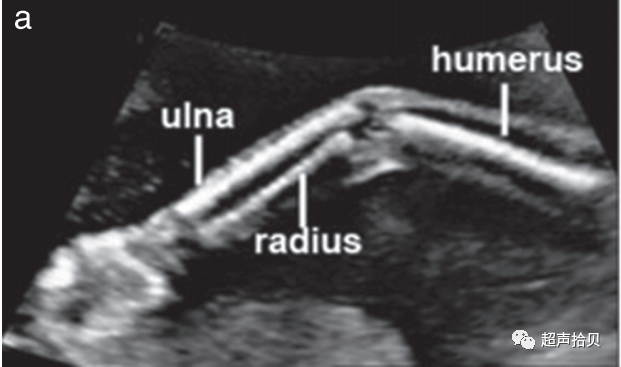

肢体和四肢

建议

• 应观察所有四个肢体的存在(良好实践证据)

• 应评估所有长骨的存在及其对称性、长度、形状、排列、位置和运动(良好实践证据)。

• 作为常规中孕期超声检查的一部分,计数手指或脚趾不是必需的(良好实践证据)。

• 除非怀疑有异常,否则测量一根股骨通常就足够了(良好实践证据)。

1. 手臂和手(图6a)以及腿和脚(图 6b ) 的存在与否 应使用系统方法进行观察记录;

2. 应检查所有四肢,注意所有长骨的存在及其对称性、长度、形状、对齐、位置和运动。

3. 作为孕中期常规超声检查的一部分,不需要计数手指或脚趾。

4. 通常,测量一根股骨就足够了,但如果有问题,则应测量所有长骨,并将测量值与标准化图表进行比较。

5. 标准检查中疑似偏离正常值应提示进行更详细的检查,以及可能的骨骼发育不良以及遗传和非遗传综合征的专家评估和咨询。

胎儿mt是什么检查什么疼吗【文献学习】【规范、指南】ISUOG实践指南:中孕期胎儿常规超声检查(2022更新)_https://www.jmylbn.com_新闻资讯_第22张

胎儿mt是什么检查什么疼吗【文献学习】【规范、指南】ISUOG实践指南:中孕期胎儿常规超声检查(2022更新)_https://www.jmylbn.com_新闻资讯_第23张

图6胎儿上(a)和(b)下肢的超声检查。上肢和下肢是否存在应常规观察记录,除非由于技术因素而不明显。